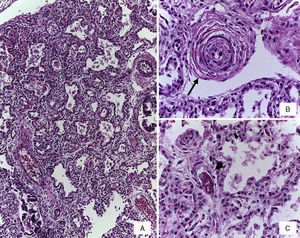

Se realizó la autopsia de una recién nacida que presentó en el aspecto exterior edema de piel y tejidos blandos, además de un defecto en la pared abdominal de 12cm de diámetro cubierto por silo de plástico con suturas íntegras (Figura 2). Cuando se retiró el silo se observó que las asas de intestino delgado se encontraban fuera de la cavidad abdominal por desproporción víscero-abdominal, estaban cubiertas por depósito de fibrina blanquecina, tenían aspecto edematoso y se encontraban unidas por adherencias. El estudio histopatólgico del aparato digestivo mostró edema de la submucosa en estómago y serosa del intestino, peritonitis crónica fibroadhesiva y aguda extensa (Figura 3). El hígado estaba aumentado de tamaño, de consistencia blanda y el parénquima de color café-amarillo. Microscópicamente se observó necrosis reciente panlobular del parénquima, en puente, con proliferación de neocolangiolos y colapso, así como colestasis hepatocelular y canalicular (Figura 4). No se identificaron inclusiones virales ni microorganismos por lo que se consideró que la necrosis fue secundaria a choque. Desde su ingreso la paciente presentaba hipoalbuminemia grave la cual se ha asociado con un pronóstico desfavorable. Se ha referido que la causa de la hipoalbuminemia es por la pérdida de líquidos de la cavidad amniótica secundaria al defecto abdominal y exposición de asas intestinales. Sin embargo, la necrosis hepática que la paciente desarrolló al final también contribuyó a agravar esta hipoalbuminemia por falta de síntesis7,8.

En la vasculatura pulmonar arterial se observaron alteraciones que corresponden a datos morfológicos de hipertensión vascular grado B y engrosamientos de los tabiques por infiltrado linfocitario por neumonitis (Figura 5). En ninguno de los cortes ni en las tinciones especiales se observaron hongos, bacterias ni inclusiones virales. Como malformación asociada se encontró una implantación anómala del uréter en la vejiga que ocasionaba dilatación de la luz y tortuosidad del mismo (Figura 6). El cerebro presentaba datos de encefalopatía hipóxica y no se encontró hemorragia intravaentricular.